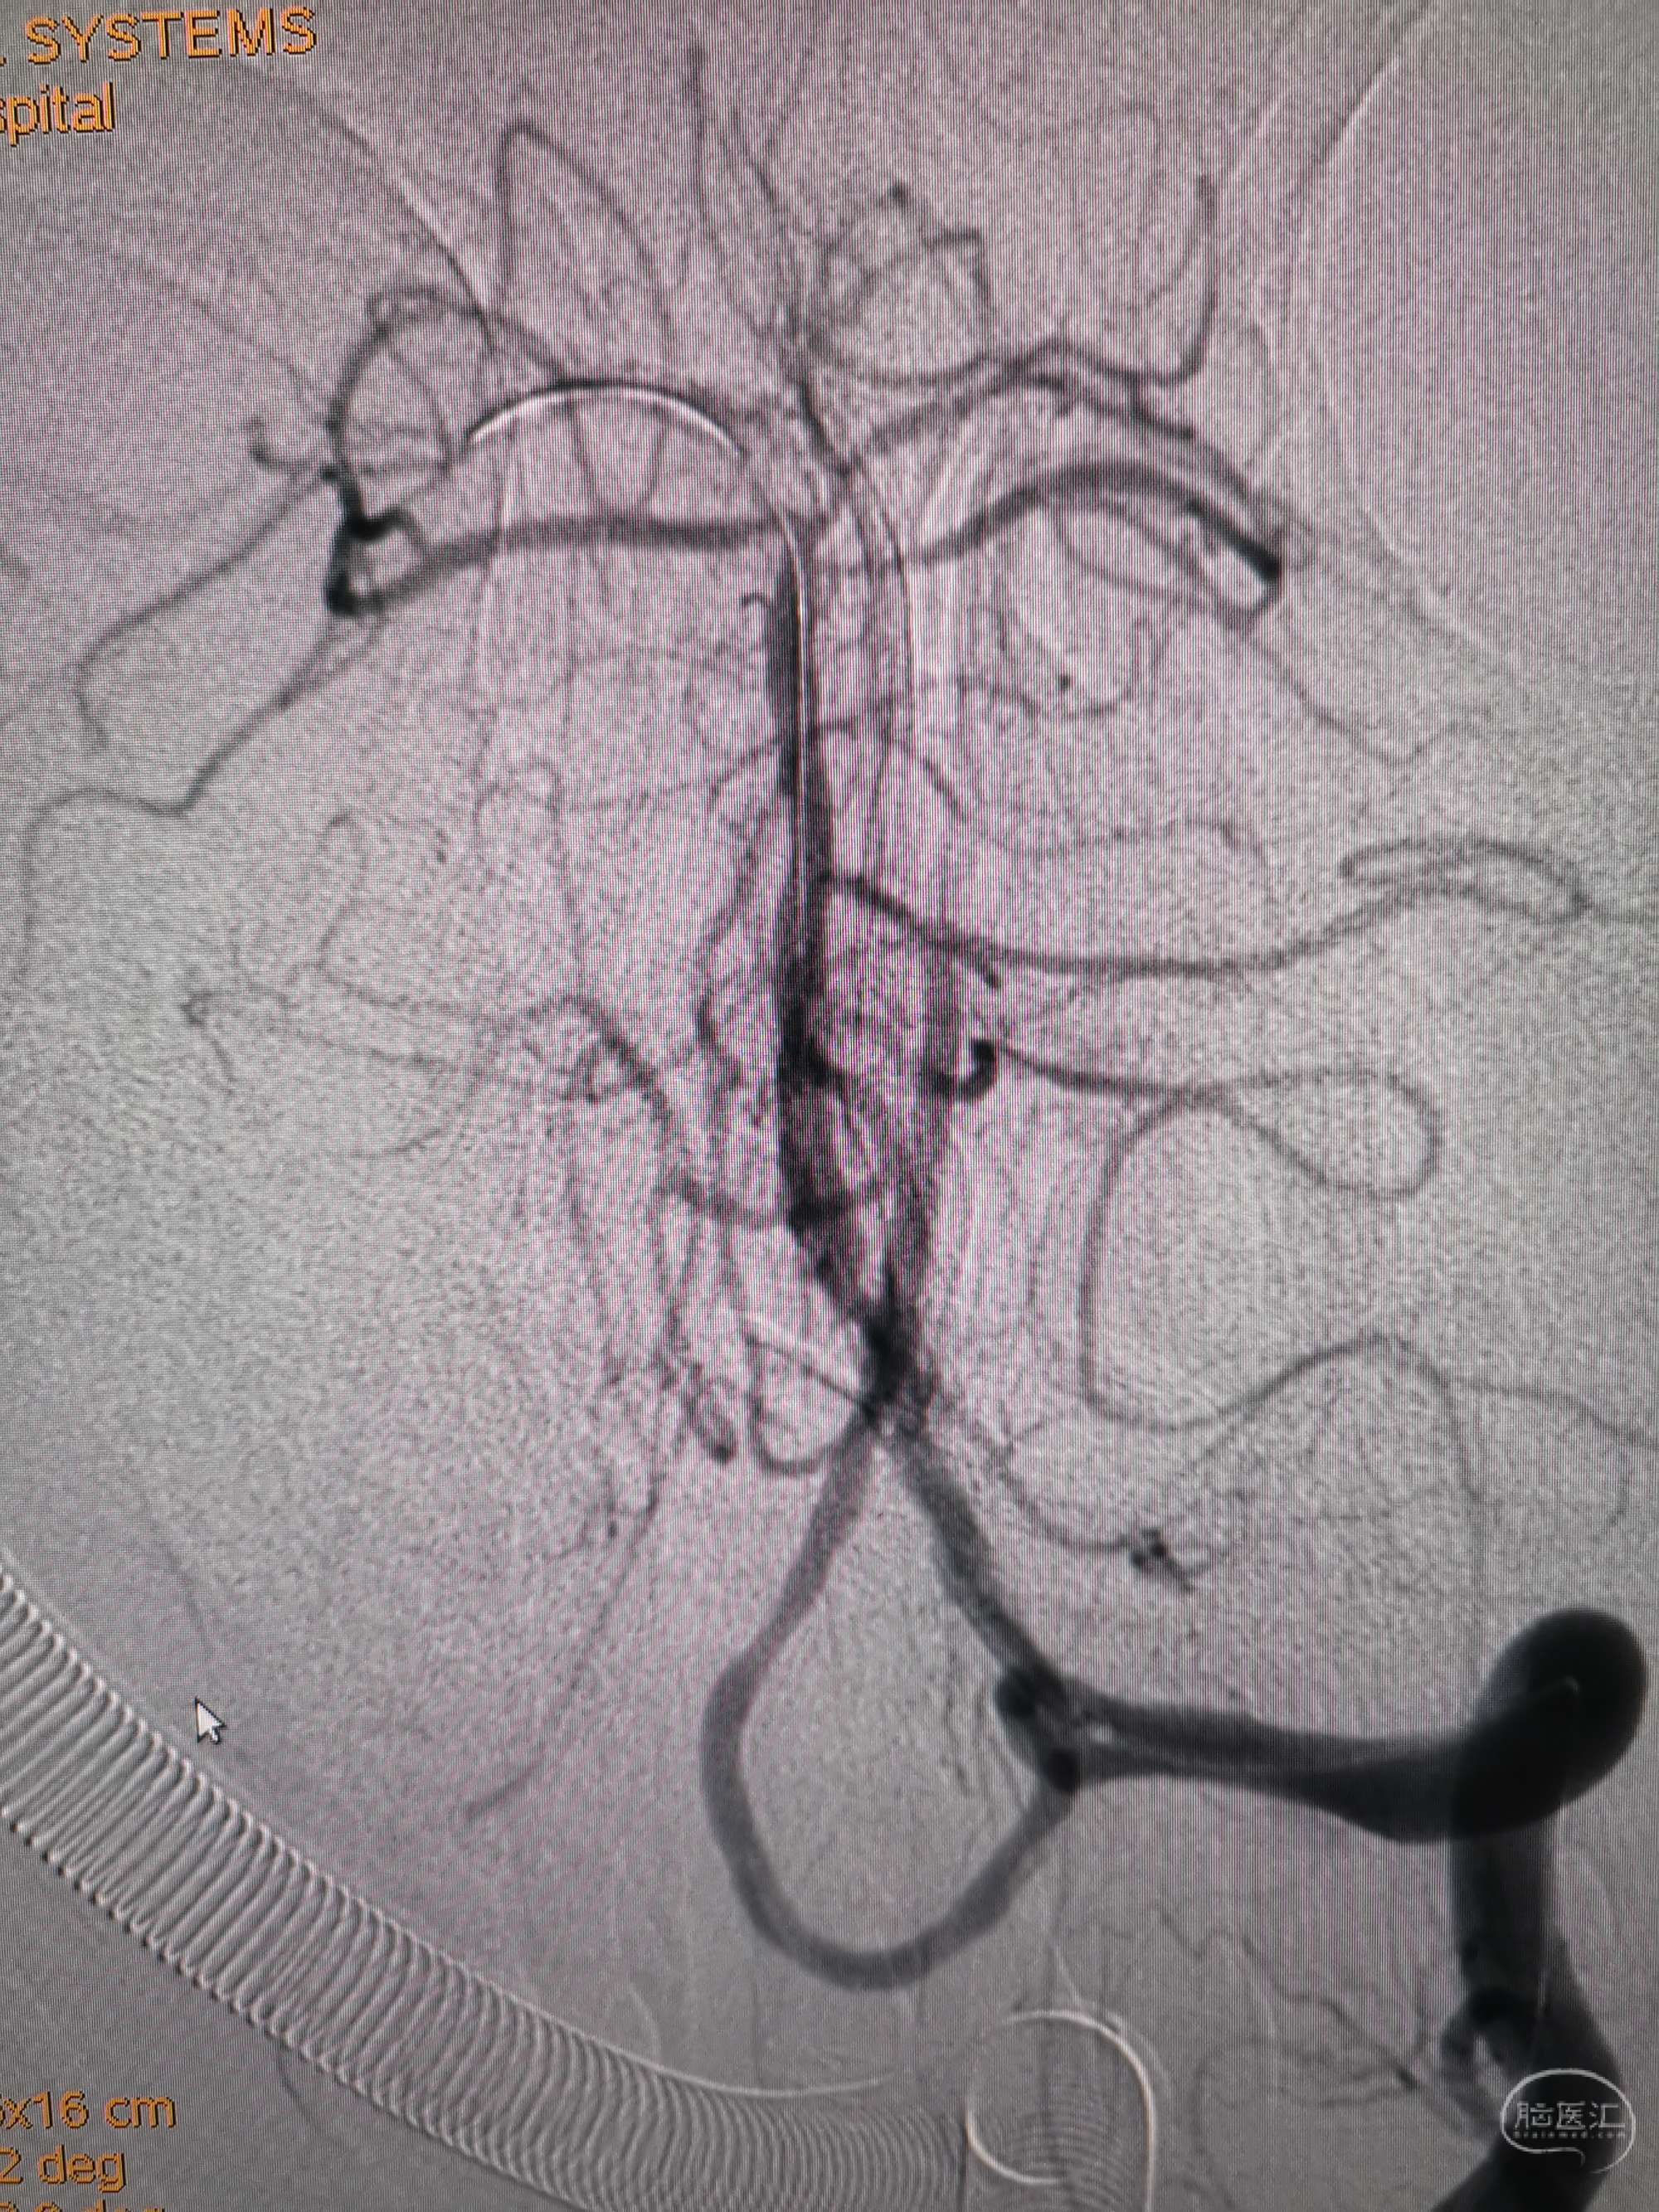

术前再次造影评估

右侧椎动脉穿支供血及左侧PICA供血较入院时略有改善,但改善不明显。故按计划行左侧椎动脉再通术